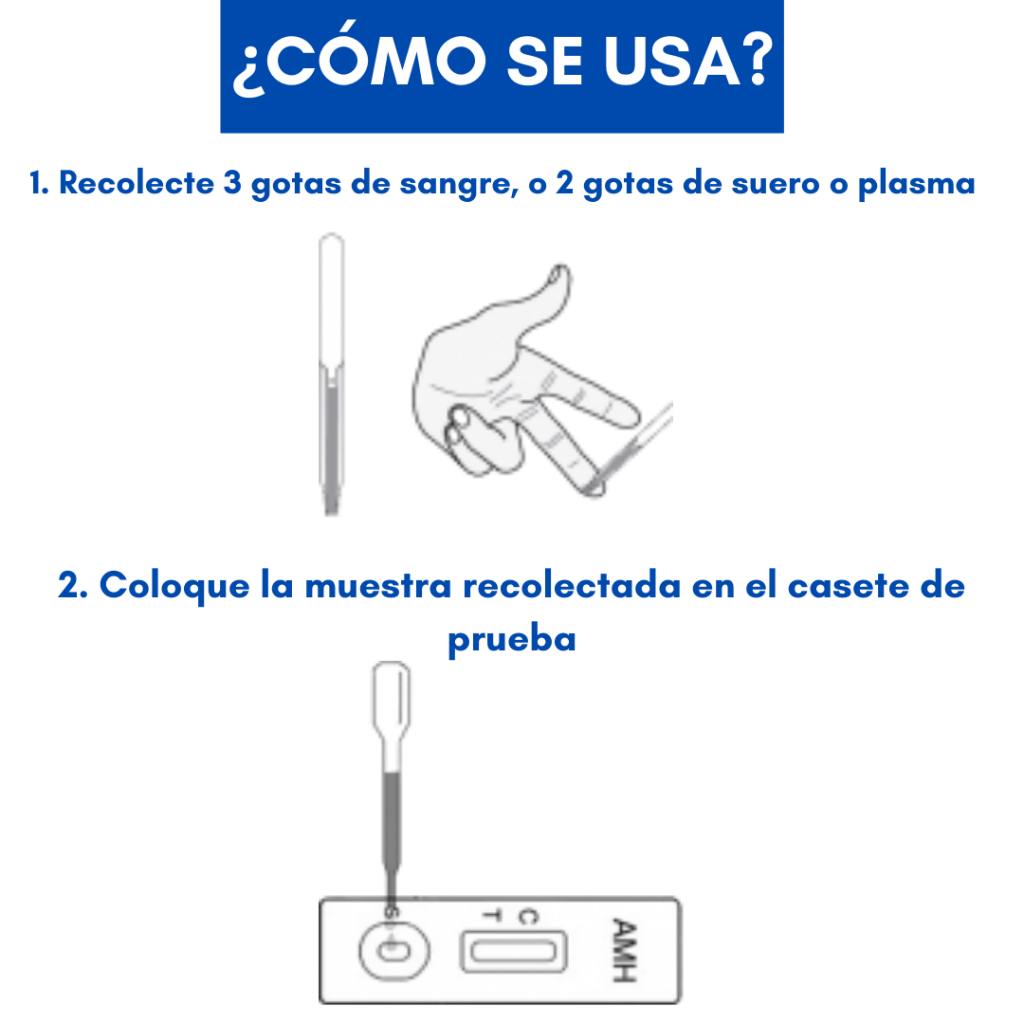

La prueba rápida AMH es un ensayo inmunocromatográfico rápido para la detección de la hormona anti-mulleriana en sangre, suero, plasma humano, para ayudar en el diagnóstico de las funciones ováricas.

Solo necesitas de tres gotas de sangre extraídas de tu dedo, o dos gotas de suero o plasma, colocar la muestra recolectada en el casete de la prueba, agregar una gota de buffer y esperar 10 minutos para interpretar los resultados. Así de rápido!

A continuación te demostramos como hacerlo de manera rápida.